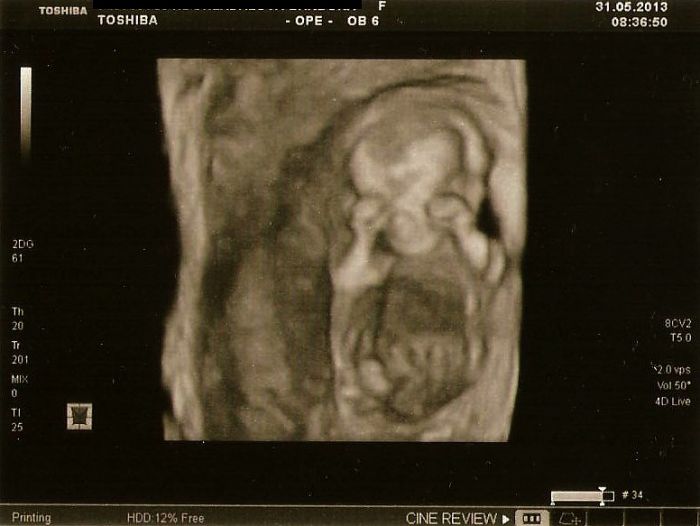

Pak ho trošku poškádlila, tak zaujal normální polohu a mohli jsme měřit. CRL máme 7,26cm a odpovídáme 13+3tt, projasnění bylo 1,3, takže prý v pořádku a stehenní kostička meřila 1 cm..Dr.mi všechno krásně popisovala a přibližovala, hlavně na obličejíčku a mrňous u toho sebou aktivně mrskal a ukazoval nám jak má dlouhý nožičky a pak se dr. smála a říká,,a teď si cpe ručičky do pusinky''..

Nakonec k mému překvapení přepla na 3D(4D) a mrňous se chvilku schovával za ručičky a pak zase mával, překvapilo mě, že to už takhle brzo bylo poměrně hezky vidět a nakonec jsme dostali 4 fotečky úplně zadarmo k ceně screeningu a z toho tři 3D..Byl to vážně úžasný zážitek a za ty peníze to určitě stálo

Přikládám 3 otečky mrňouska,první je z kontroly u mého dr.jak tam hačá,na té další se musím smát jak ukazuje chodidlo a druhou nohou se snaží prokopnout ven z bříška

Na té 3D si úspěšně schovává obličejík ručičkama, stydlínek náš malinkej